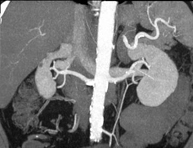

- Angio-TC arterias renales  Prueba diagnóstica no invasiva que consiste en el estudio de las arterias renales obteniendo imágenes de alta definición anatómica mediante el empleo de un equipo de TC (Tomografía Computarizada) y de contraste yodado. La calidad de las imágenes permite realizar reconstrucciones en 2D y 3D gracias a estaciones de trabajo especializadas en el estudio arterial. Esta prueba está indicada, por ejemplo, en aquellos pacientes que sufren de HTA refractaria al tratamiento, en pacientes con lesiones renales para tener un mapa "vascular" pre-quirúrgico, etc. Prueba diagnóstica no invasiva que consiste en el estudio de las arterias renales obteniendo imágenes de alta definición anatómica mediante el empleo de un equipo de TC (Tomografía Computarizada) y de contraste yodado. La calidad de las imágenes permite realizar reconstrucciones en 2D y 3D gracias a estaciones de trabajo especializadas en el estudio arterial. Esta prueba está indicada, por ejemplo, en aquellos pacientes que sufren de HTA refractaria al tratamiento, en pacientes con lesiones renales para tener un mapa "vascular" pre-quirúrgico, etc.

- Angio TC d'artèries renals Prova diagnòstica no invasiva que consisteix en l'estudi de les artèries renals amb l'obtenció d'imatges d'alta definició anatòmica mitjançant l'ús d'un equip de TC (Tomografia Computaritzada) i contrast iodat. La qualitat de les imatges permet realitzar reconstruccions en 2D i 3D gràcies a estacions de treball especialitzades en l'estudi arterial. Aquesta prova està indicat en aquells pacients que pateixen HTA refractària al tractament, en pacients amb lesions renals que tenen un mapa vascular prequirúrgic, etc. Prova diagnòstica no invasiva que consisteix en l'estudi de les artèries renals amb l'obtenció d'imatges d'alta definició anatòmica mitjançant l'ús d'un equip de TC (Tomografia Computaritzada) i contrast iodat. La qualitat de les imatges permet realitzar reconstruccions en 2D i 3D gràcies a estacions de treball especialitzades en l'estudi arterial. Aquesta prova està indicat en aquells pacients que pateixen HTA refractària al tractament, en pacients amb lesions renals que tenen un mapa vascular prequirúrgic, etc.